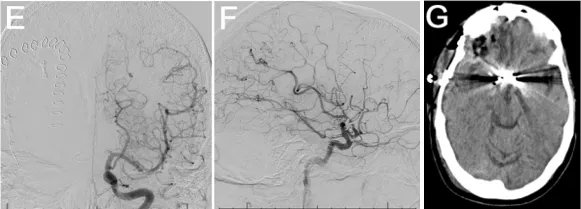

数字减影血管造影(DSA)显示,A1-A2端及前交通动脉瘤周围存在显著的放射性血管炎。DSA侧位像显示动脉瘤(箭头指示)。DSA侧位像显示放射性血管炎,表现为血管分支减少及多处血管狭窄(箭头指示)。DSA正位像显示2年前Wada试验时未见动脉瘤或血管炎性改变。血管造影亦证实存在放射性血管炎。

患者随后接受经右侧额部翼点入路开颅术行动脉瘤夹闭术,手术过程顺利。术后影像证实动脉瘤闭塞有效,无并发症。术后脑灌注成像显示一处术前已知的陈旧性脑梗死区域。患者术后接受随访监测,时长23.9个月。

鉴于患者有明确的放射性血管病变病史,决定采用手术方式治疗该动脉瘤。考虑到患者血管脆性较高,开颅夹闭术被认为是动脉瘤治疗的最佳选择。尽管也考虑了血管内治疗,但开放性血管治疗被认为能提供更长久的疗效,并降低动脉瘤再生的风险。